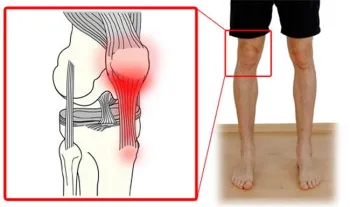

The diagram of the Patellar tendon at the knee is commonly injured.